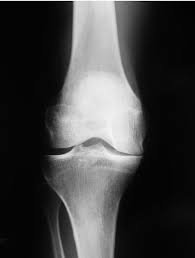

Osteoarthritis of the Knee

Cause

Gradual wear and tear of the cartilage, leading to bone-on-bone friction, common in older adults or individuals with excess weight.

Symptoms

• Dull, aching pain on the inner side of the knee.

• Morning stiffness or stiffness after prolonged inactivity.

• Cracking or grinding sounds (crepitus) during knee movement.

• Pain that worsens with activity and improves with rest.

• Swelling and tenderness around the joint, especially after long walks.